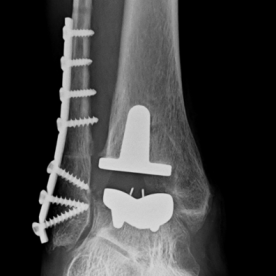

Röntgenbilder